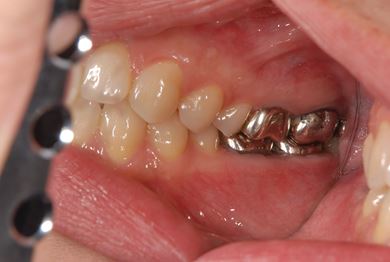

| 性別/年齢 | 女性 / 39歳 | ||||||||||||||||||||||||||||||||

| 主訴 | 右奥歯の虫歯と、右奥のインプラント治療について相談。 | ||||||||||||||||||||||||||||||||

| 治療方針 | 右下奥欠損部分をインプラント治療にて、機能的・審美的回復を行う。 | ||||||||||||||||||||||||||||||||

| 治療内容 | インプラント1本、ハイブリッドセラミッククラウン1本 | ||||||||||||||||||||||||||||||||